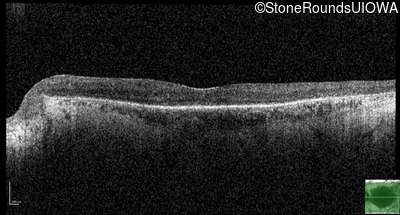

Optical Coherence Tomography - Left - 20/40 +1

Exemplar / OCT Stack